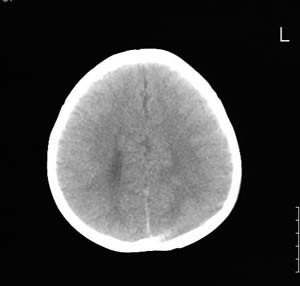

以下是引用lixi在2006-12-5 21:06:00的发言:[br]1、dandy-walker变异。2、胼胝体发育不良。

以下是引用zhuoshandiao在2006-12-5 21:41:00的发言:[br]胼胝体发育不良应该是肯定的。另外考虑dand-walker畸形。

以下是引用卜一在2006-12-5 22:30:00的发言:[br]支持考虑:1、dandy-walker变异。2、胼胝体发育不良

以下是引用wangzhanshuang在2006-12-5 21:03:00的发言:[br]后颅窝蛛网膜囊肿,胼胝体发育不良